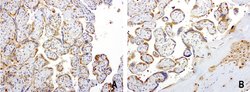

| Applications | Immunocytochemistry, Immunofluorescence, Immunohistochemistry (Paraffin) |